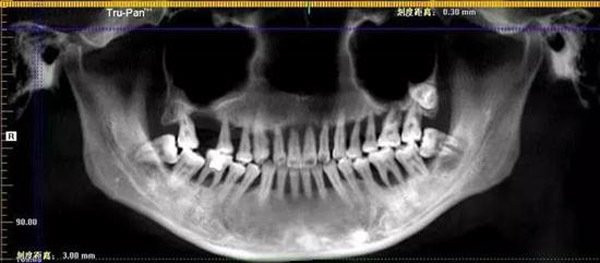

Hình ảnh cho thấy hàm răng trên của Tiểu Manh đã bị tổn thương.

Sau khi thăm khám, bác sĩ kết luận cô bị viêm nha chu nặng và phải nhổ bỏ toàn bộ hàm răng trên. Nghe tin, Tiểu Manh ngồi lặng người trong phòng khám 20 phút, sốc không nói nên lời.

Với tình hình hiện tại, răng của Tiểu Manh hầu như không thể tiếp tục sử dụng mà phải nhổ bỏ và trồng răng mới thay thế.